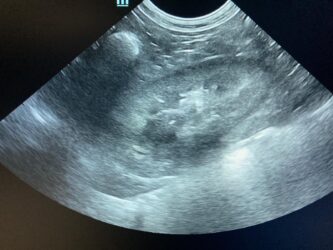

Dimitri, CV, 9.6kg, 11j, MC, bijgeruis 4/6 waarvoor hij vetmedin krijgt en opgevolgd wordt door cardioloog:

21/08/2025: Bij buurtcollega aangeboden voor hematurie. Plast vlot, op’t einde bloed te zien. Mevr. kookt zelf voor hem. Echo gehad + UOZ (geen idee hoe dit werd gecollecteerd) gedaan. Veel bloed in de…